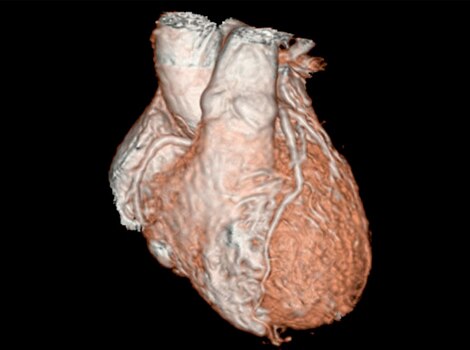

Revolution™ CT & CardioGraphe4

Achieve one-beat, whole heart acquisition for imaging or comprehensive cardiac assessment with or without beta blockers at any heart rate.5

Revolution™ CT & CardioGraphe7

Achieve one-beat, whole heart acquisition for imaging or comprehensive cardiac assessment with or without beta blockers at any heart rate.8

Revolution™ CT & CardioGraphe3

Achieve one-beat, whole heart acquisition for imaging or comprehensive cardiac assessment with or without beta blockers at any heart rate.4